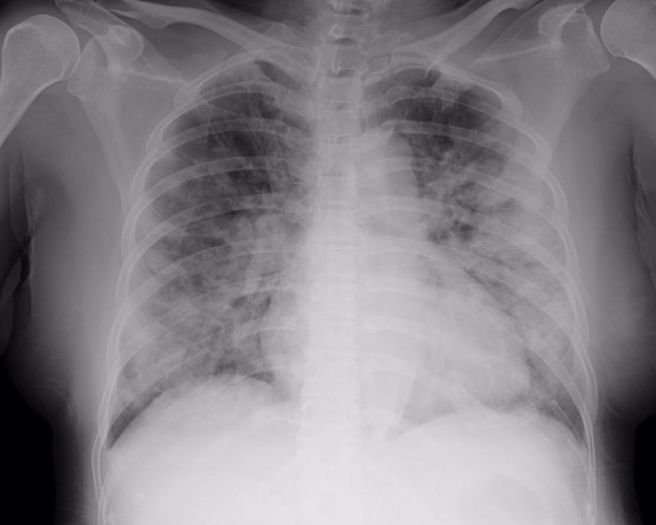

麦迪纳昨天表示,患者出现「严重呼吸系统疾病,出现双侧性肺炎(bilateral pneumonia)…跟COVID非常像」。